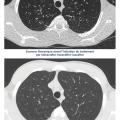

Place de l’imagerie dans le suivi de la mucoviscidose

La pathologie respiratoire au cours de la mucoviscidose représente encore l’essentiel de la morbidité et de la mortalité.1 La répétition des exacerbations respiratoires depuis l’enfance jusqu’à l’âge adulte accélère le déclin de la fonction respiratoire et favorise l’apparition de lésions radiologiques irréversibles telles que les…